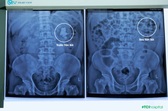

Nốt tăng âm là một vệt sáng nhỏ được nhìn thấy khi siêu âm tim thai. Nó là sự hóa quặng lắng đọng canxi ở cơ tim.

Siêu âm tim thai nhi có nốt tăng âm thường được bắt gặp trong khoảng 3-5% của những người mang thai bình thường và nó không ảnh hưởng gì đến sức khỏe.

Các nốt tăng âm trong tim thai nhi thường có cấu trúc khá nhỏ, tìm thấy trong hơn 90% trường hợp ở thất trái và có kích thước từ 1-4mm. Mẹ đừng quá lo lắng khi phát hiện tình trạng bé yêu nhà mình có nốt tăng âm ở tim. Bởi lẽ, nó không ảnh hưởng gì nhiều đến chức năng của tim đâu mẹ nhé!

Thai nhi có nốt tăng âm đơn thuần ở tim thì thường tiên lượng tốt. Ở thai kỳ tháng thứ 3, có thể nốt tăng âm sẽ tự mất đi mà không cần phải can thiệp bất kỳ phương pháp y khoa nào.

Nốt tăng âm trong buồng tim nếu đơn độc không kèm theo bất kỳ bất thường nào khác thì đa số thai bình thường. Nhưng nếu nốt tăng âm buồng tim đi kèm với những đối tượng có nguy cơ cao như: mẹ lớn tuổi, có con trước bị bất thường nhiễm sắc thể hoặc thai có bất thường khác thì nốt tăng âm sẽ làm tăng nguy cơ bất thường về nhiễm sắc thể, đặc biệt là hội chứng Down.